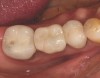

A mandibular right first molar was extracted due to an advanced Class III furcation and an irreversible pulpitis—a combination lesion. An immediate implant placement protocol was elected, and a PEEK abutment was placed on the implant (Figure 1). After 3 months of healing, a scan body was placed on the osseointegrated implant (Figure 2 and Figure 3), and an intraoral scan was taken (TRIOS Pod) (Figure 4) for the fabrication of a screw-retained crown.

Once the STL file generated from the intraoral scanner was sent to the laboratory (Figure 5), the technician used proprietary software to design the crown (Figure 6 through Figure 8), mill the crown, and digitally print a SLA model (Dental SG, Formlabs, www.formlabs.com) (Figure 9 through Figure 11), and then finish the crown on the digitally printed model. The angulated screw-channel full-zirconia crown (Nobel Biocare) (Figure 12) was seated, and contacts were evaluated intraorally and adjusted extraorally. The screw-retained crown was torqued to 35 Ncm2, and the screw access was sealed (Figure 13 through Figure 15).

Fig 3. Confirmation of seating of scan body.

Figure 3

Fig 13. Screw-retained implant crown replacing missing first molar, occlusal view.

Figure 13

Fig 14. Screw-retained implant crown replacing missing first molar, buccal view.

Figure 14

Fig 15. Final restoration of mandibular right first molar.

Figure 15